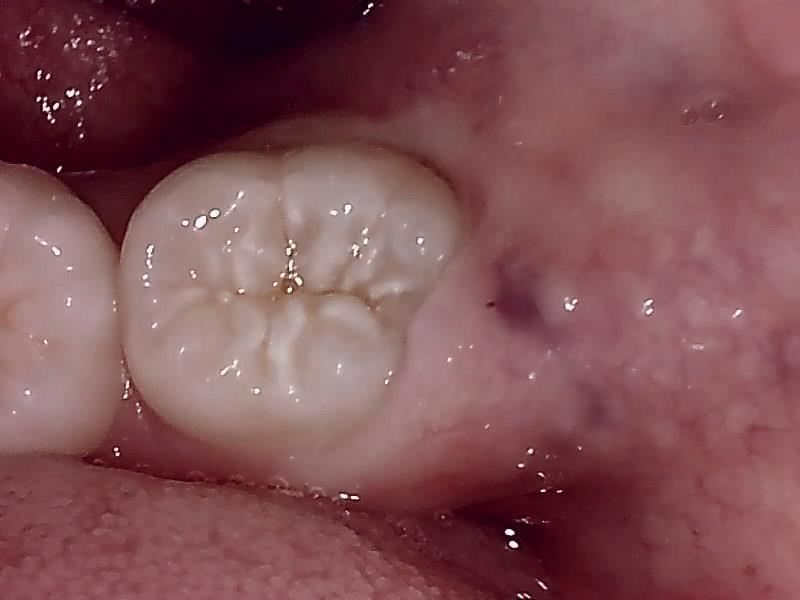

術後 治癒

【After】

術後の痺れなどもなくとても良好です。

抜歯後、経過良好です。